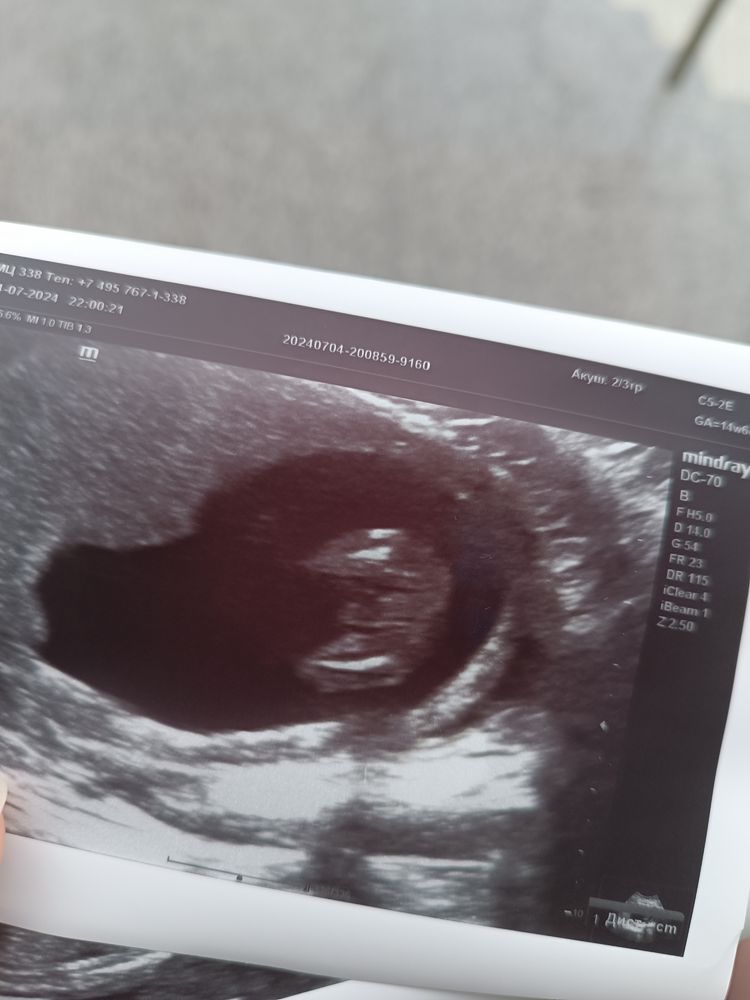

УЗИ 15-16 недель. Мальчик 💙

Сделали УЗИ на сроке 15+4. Переживала за шейку матки. С ней всё хорошо 50мм. По УЗИ всё отлично. Идём срок в срок по скриннингу. А так же врач сразу сказал что у нас такое пистолетище что ни с чем не спутаешь😃. Что подтверждает слова врача на скриннинге.Муж счастлив))) Фото пистолета прилагается😆

Вот бы еще понять куда смотреть🙈😂